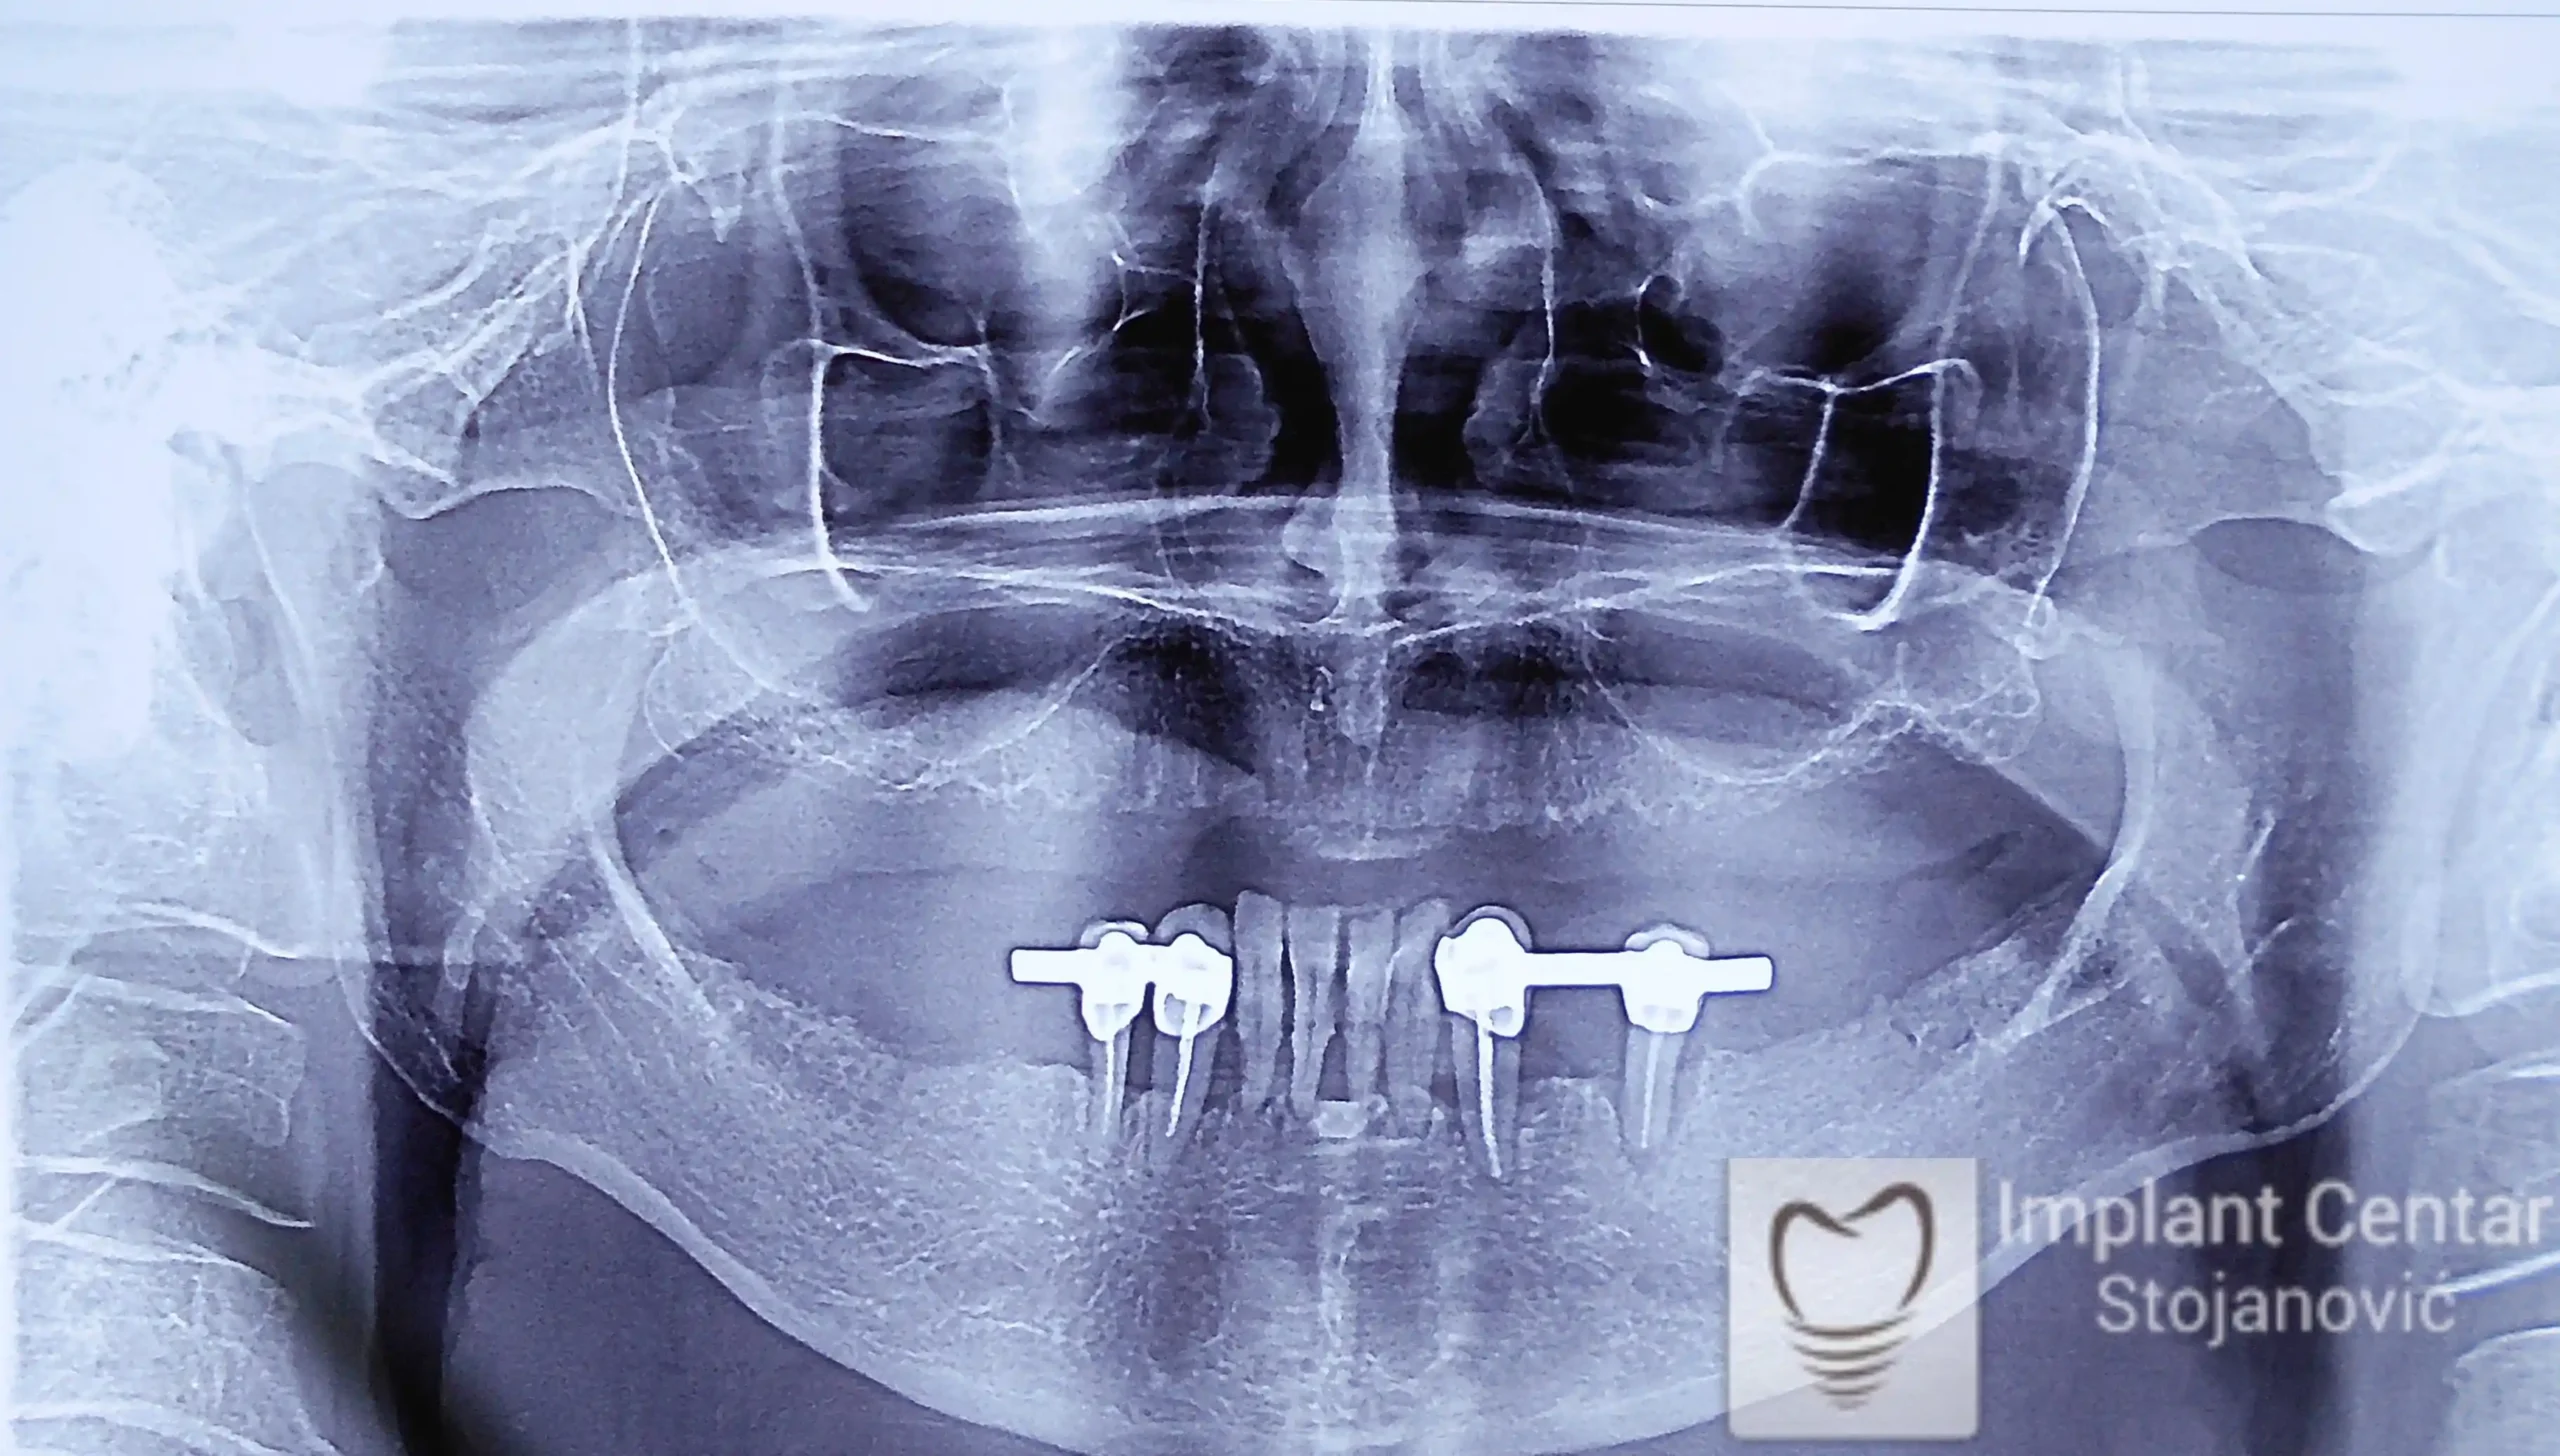

Pacijent sa rascepom usne, nepca i alveolarnog grebena uspešno je rehabilitovan fiksnim protetskim radom na implantatima. Pre dolaska u našu ordinaciju, pacijent je u gornjoj vilici nosio totalnu protezu preko preostalih zuba, dok je u donjoj vilici bio zbrinut parcijalnom mobilnom protezom. Tokom višegodišnje potrage za adekvatnim rešenjem, pacijent nije uspeo da pronađe zadovoljavajuću terapijsku opciju ni u zemlji ni u inostranstvu.

Nakon detaljnog kliničkog pregleda i analize radioloških snimaka, izrađen je sveobuhvatan plan terapije sa ciljem uklanjanja mobilnih proteza i postizanja maksimalne funkcionalne i estetske rehabilitacije. Zbog loše biološke vrednosti preostalih zuba, doneta je odluka o njihovom vađenju i ugradnji dentalnih implantata.

Poseban terapijski izazov predstavljalo je premošćavanje defekta nastalog usled rascepa, kao i ograničena količina raspoložive kosti u gornjoj vilici. Primenom većeg broja implantata i odgovarajućih procedura nadoknade kosti, postignuta je stabilna osnova za fiksni protetski rad.